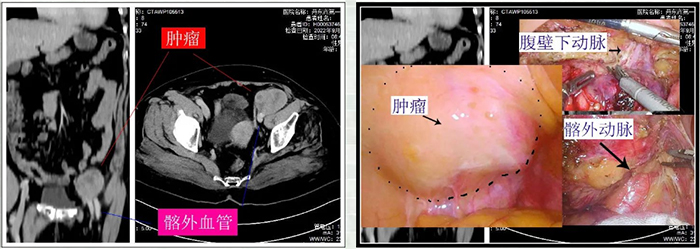

患者女性,年龄60岁,因后腰部不适入院,经进一步完善检查,术前确诊为腹膜后肿瘤。经我院普外一科医疗团队的术前评估,并协同泌尿外科、麻醉科等多学科MDT小组会诊后,为了最大限度的提高患者术后生活质量,吴瑶强副院长带领医疗团队决定实施我市首例“腹腔镜下腹膜后肿瘤切除术”,在腹腔镜下为其完成手术。

经手术探查发现,该肿物位于腹膜后,直径约 6*8厘米,包膜完整,与后腹膜的髂血管关系紧密。由于腹膜后有丰富的血管和神经,该区域的肿瘤患者就诊时,肿物常常已侵及大血管或神经,手术剥离中,稍有不慎就会造成副损伤导致大出血。即便采用传统开腹手术,视野清晰,难度也很大。在腹腔镜下,切除与周围脏器关系如此复杂的肿瘤,更是难上加难。术中,吴瑶强团队可谓谨小慎微,步步为营。最终,肿瘤完整切除,由于其切口小,疼痛轻,术后第一天,患者就可以无障碍下床活动。

术后病理诊断为低度恶性间质肿瘤 ,三天后患者顺利出院。